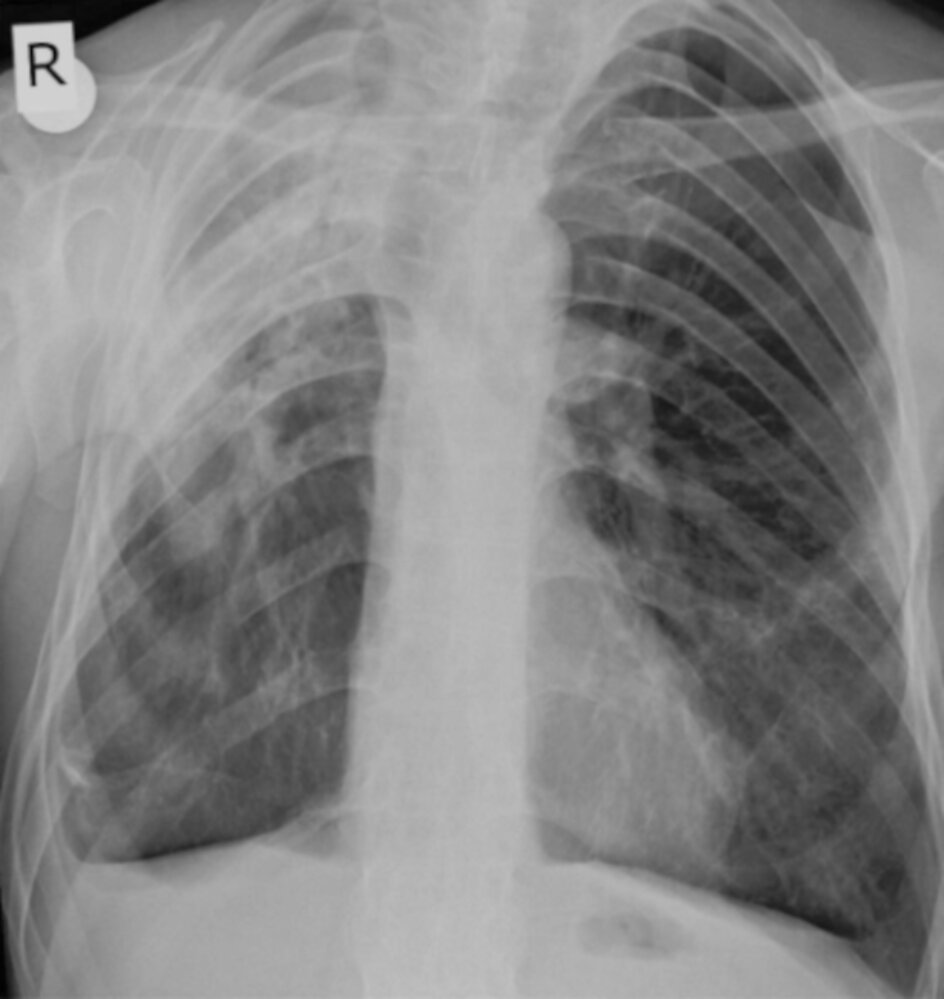

• Restrictive pulmonary disease

• Due to decreased mobility of the thoracic spine and costovertebral joints

• Secondary to apical pulmonary fibrosis or more widespread interstitial lung disease [6]

Restrictive lung disease

• Dyspnea

• Limited chest expansion

• Fine crackles on auscultation

• Pulmonary function testing: restrictive disease pattern

• HRCT [6]

• Ankylosis of costosternal and costovertebral joints

• Apical (upper lobe) fibrosis

• Interstitial lung disease

• Restricted chest expansion and spine mobility → breathing difficulties

• Lungs: fibrosis of upper lobes (apical fibrosis) [6]